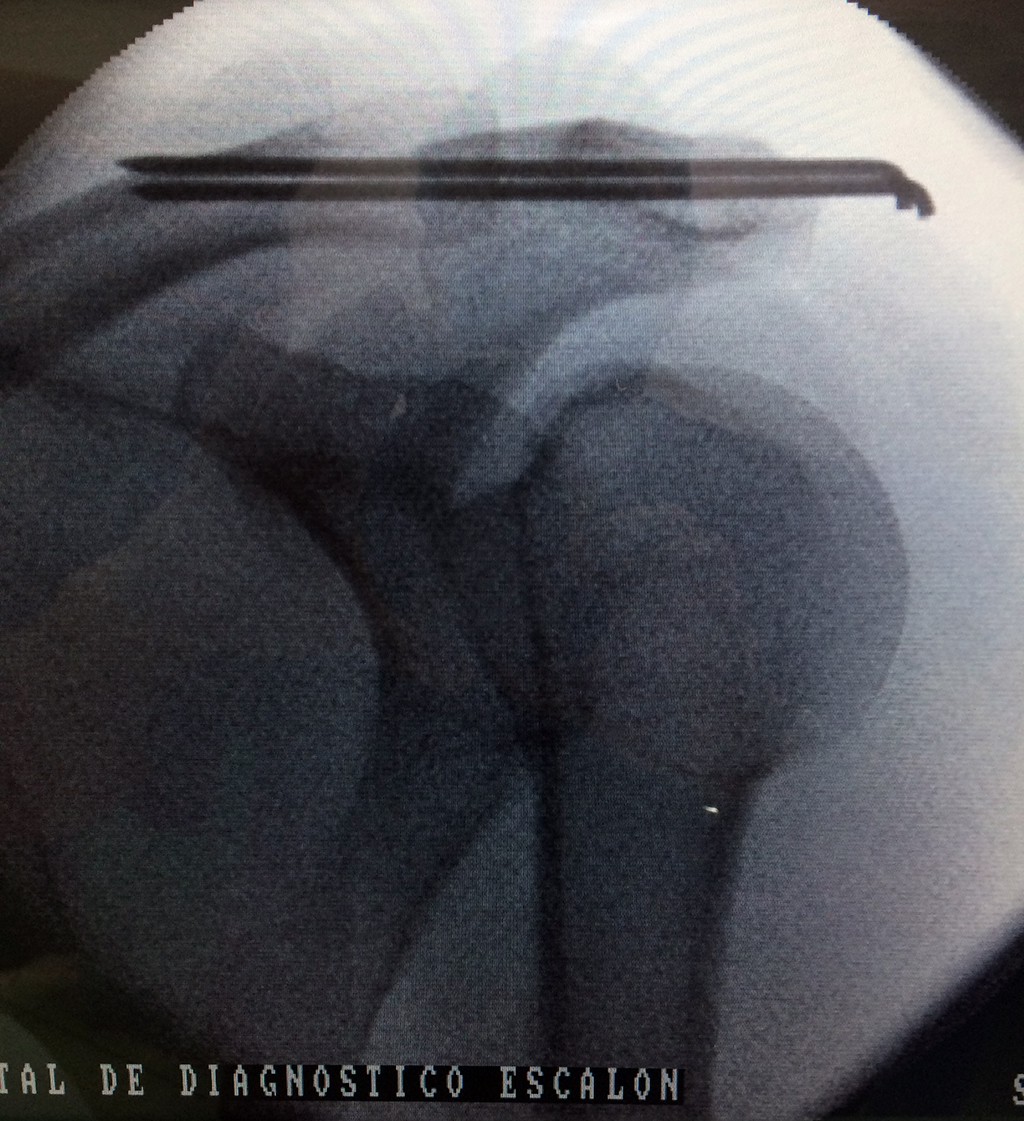

La clavícula es un hueso largo, con forma de "S" itálica, situado en la parte anterosuperior del tórax. Junto con la escápula forman la cintura escapular. Se puede palpar por toda su longitud y se extiende del esternón al acromion de la escápula, siguiendo una dirección oblicua lateral y posterior.

Se considera el único medio de unión entre el miembro superior y el tórax. A pesar de su aspecto, similar al de un hueso largo, posee una estructura semejante a la de un hueso plano, ya que carece de epífisis y de diáfisis, lo que la harían entrar dentro de la clasificación de hueso largo. Carece de un canal medular propiamente dicho.